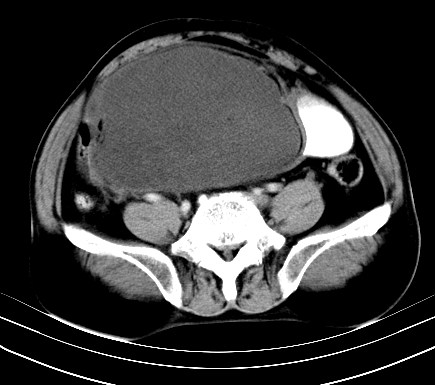

标题: CT19729B:男,74岁,因腿疼就诊,查体触腹部肿物,

增强扫描

延时期

【ct表现】

1、肿块巨大,往往位于腹膜后,长大后才引起症状而就诊;那么位于腹膜后的肿瘤80%为恶性肿瘤。

2、实性肿瘤,增强扫描轻度不均强化,实性肿瘤一般不是好东西。

3、肿瘤边缘似见少许脂肪样密度。

4、腹膜后未见肿大淋巴结,但肿瘤于临近的肠管及组织接触紧密。

【诊断】

腹部占位,考虑位于腹膜后的恶性肿瘤,脂肪肉瘤(实体型)可能性大。

术后病理结果:腹膜后脂肪肉瘤。